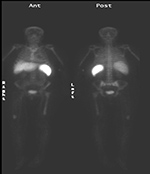

Brown fat or brown adipose tissue (BAT) and white adipose tissue are the two kinds of fat (adipose tissue) found in mammals. Brown fat is especially abundant in newborns with its primary function being to generate body heat. Brown fat cells contain many small droplets of lipids and a high number of mitochondria which make it brown. It contains more capillaries than white fat having a greater need for oxygen delivery. Brown fat becomes less common as one ages. It is still present in adults in the upper chest, neck, paraspinal, and suprarenal regions and is more metabolically active with cold exposure (figure 34).

63 year-old woman with right femoral hardware for 3 years presented with right leg pain. Whole body Tc-99m HMPAO tagged WBC (A) scan demonstrated focal abnormal activity in the distal right femur which may represent infection or focal marrow. Tc99m sulphur colloid bone marrow scan (B) four weeks later demonstrates similar focal uptake in the distal right femur confirming the etiology as uptake in displaced marrow and not infection. 60 year-old man with history of lung cancer and left hip arthroplasty suffered from stiffness in the left hip region. Axial CT, FDG PET, fused axial, and coronal PET-CT demonstrates increased uptake of FDG in heterotopic ossification in the musculature of the left thigh. 30 year-old woman with history of lymphoma. Axial CT, PET, PET-CT fused, and PET MIP images demonstrate intense FDG activity in the bilateral neck and paravertebral regions with a symmetrical distribution. Cross-sectional images clearly show that activity in the neck corresponds to fat and therefore consistent with brown fat activity. Brown fat activity is seen more commonly in younger patients and is also increased in response to hypothermia (so keep patients warm both pre and post injection of FDG).